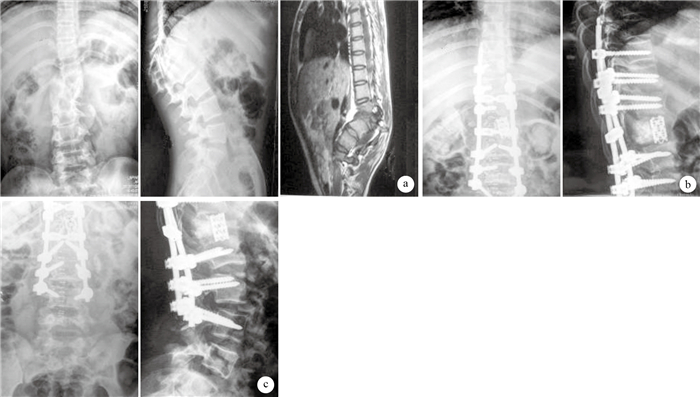

患者均順利完成手術,手術時間3 h 30 min~5 h 30 min,平均4.3 h;術中出血量600~2 000 mL,平均860 mL。術后切口均Ⅰ期愈合。術后麻醉清醒時有3例脊髓神經損傷,由術前Frankel分級D級加重至C級,給予激素、脫水和神經營養藥物治療后約1周恢復;術后3 d 2例出現肺部感染,經抗感染對癥處理后治愈。13例均獲隨訪,隨訪時間12~48個月,平均17個月。術后3個月7例紅細胞沉降率恢復至正常范圍,余6例至7個月恢復至正常范圍。X線片及CT示術后10~20個月,平均14個月截骨處達骨性愈合。隨訪期間內固定物無松動、移位、斷裂等發生;術前結核癥狀、體征均消失,未見結核病灶復發征象,患者恢復正常生活。見圖 1。術后1周神經功能Frankel分級為B級1例、C級10例、D級2例,末次隨訪時為D級1例、E級12例,均較術前顯著改善(P < 0.05),末次隨訪與術后1周比較差異亦有統計學意義(P < 0.05)。術后1周及末次隨訪時脊柱后凸Cobb角分別為(22.38±1.76)°和(22.15±1.83)°,與術前比較差異均有統計學意義(P < 0.05);末次隨訪時與術后1周比較,差異無統計學意義(P > 0.05)。術后1周及末次隨訪時VAS評分分別為(4.08±0.76)分和(0.62±0.14)分,與術前比較差異均有統計學意義(P < 0.05);末次隨訪時與術后1周比較,差異亦有統計學意義(P < 0.05)。